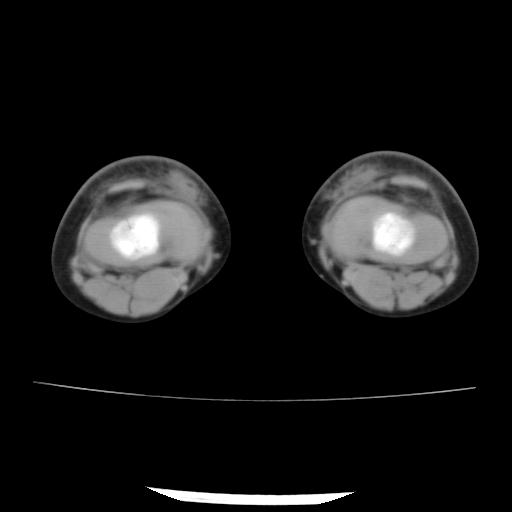

标题: PED0931:男,5岁,发现双小腿软组织肿块1年,质地中等,无 [打印本页]

标题: PED0931:男,5岁,发现双小腿软组织肿块1年,质地中等,无

多发性神经纤维瘤?

考虑多发性神经纤维瘤.